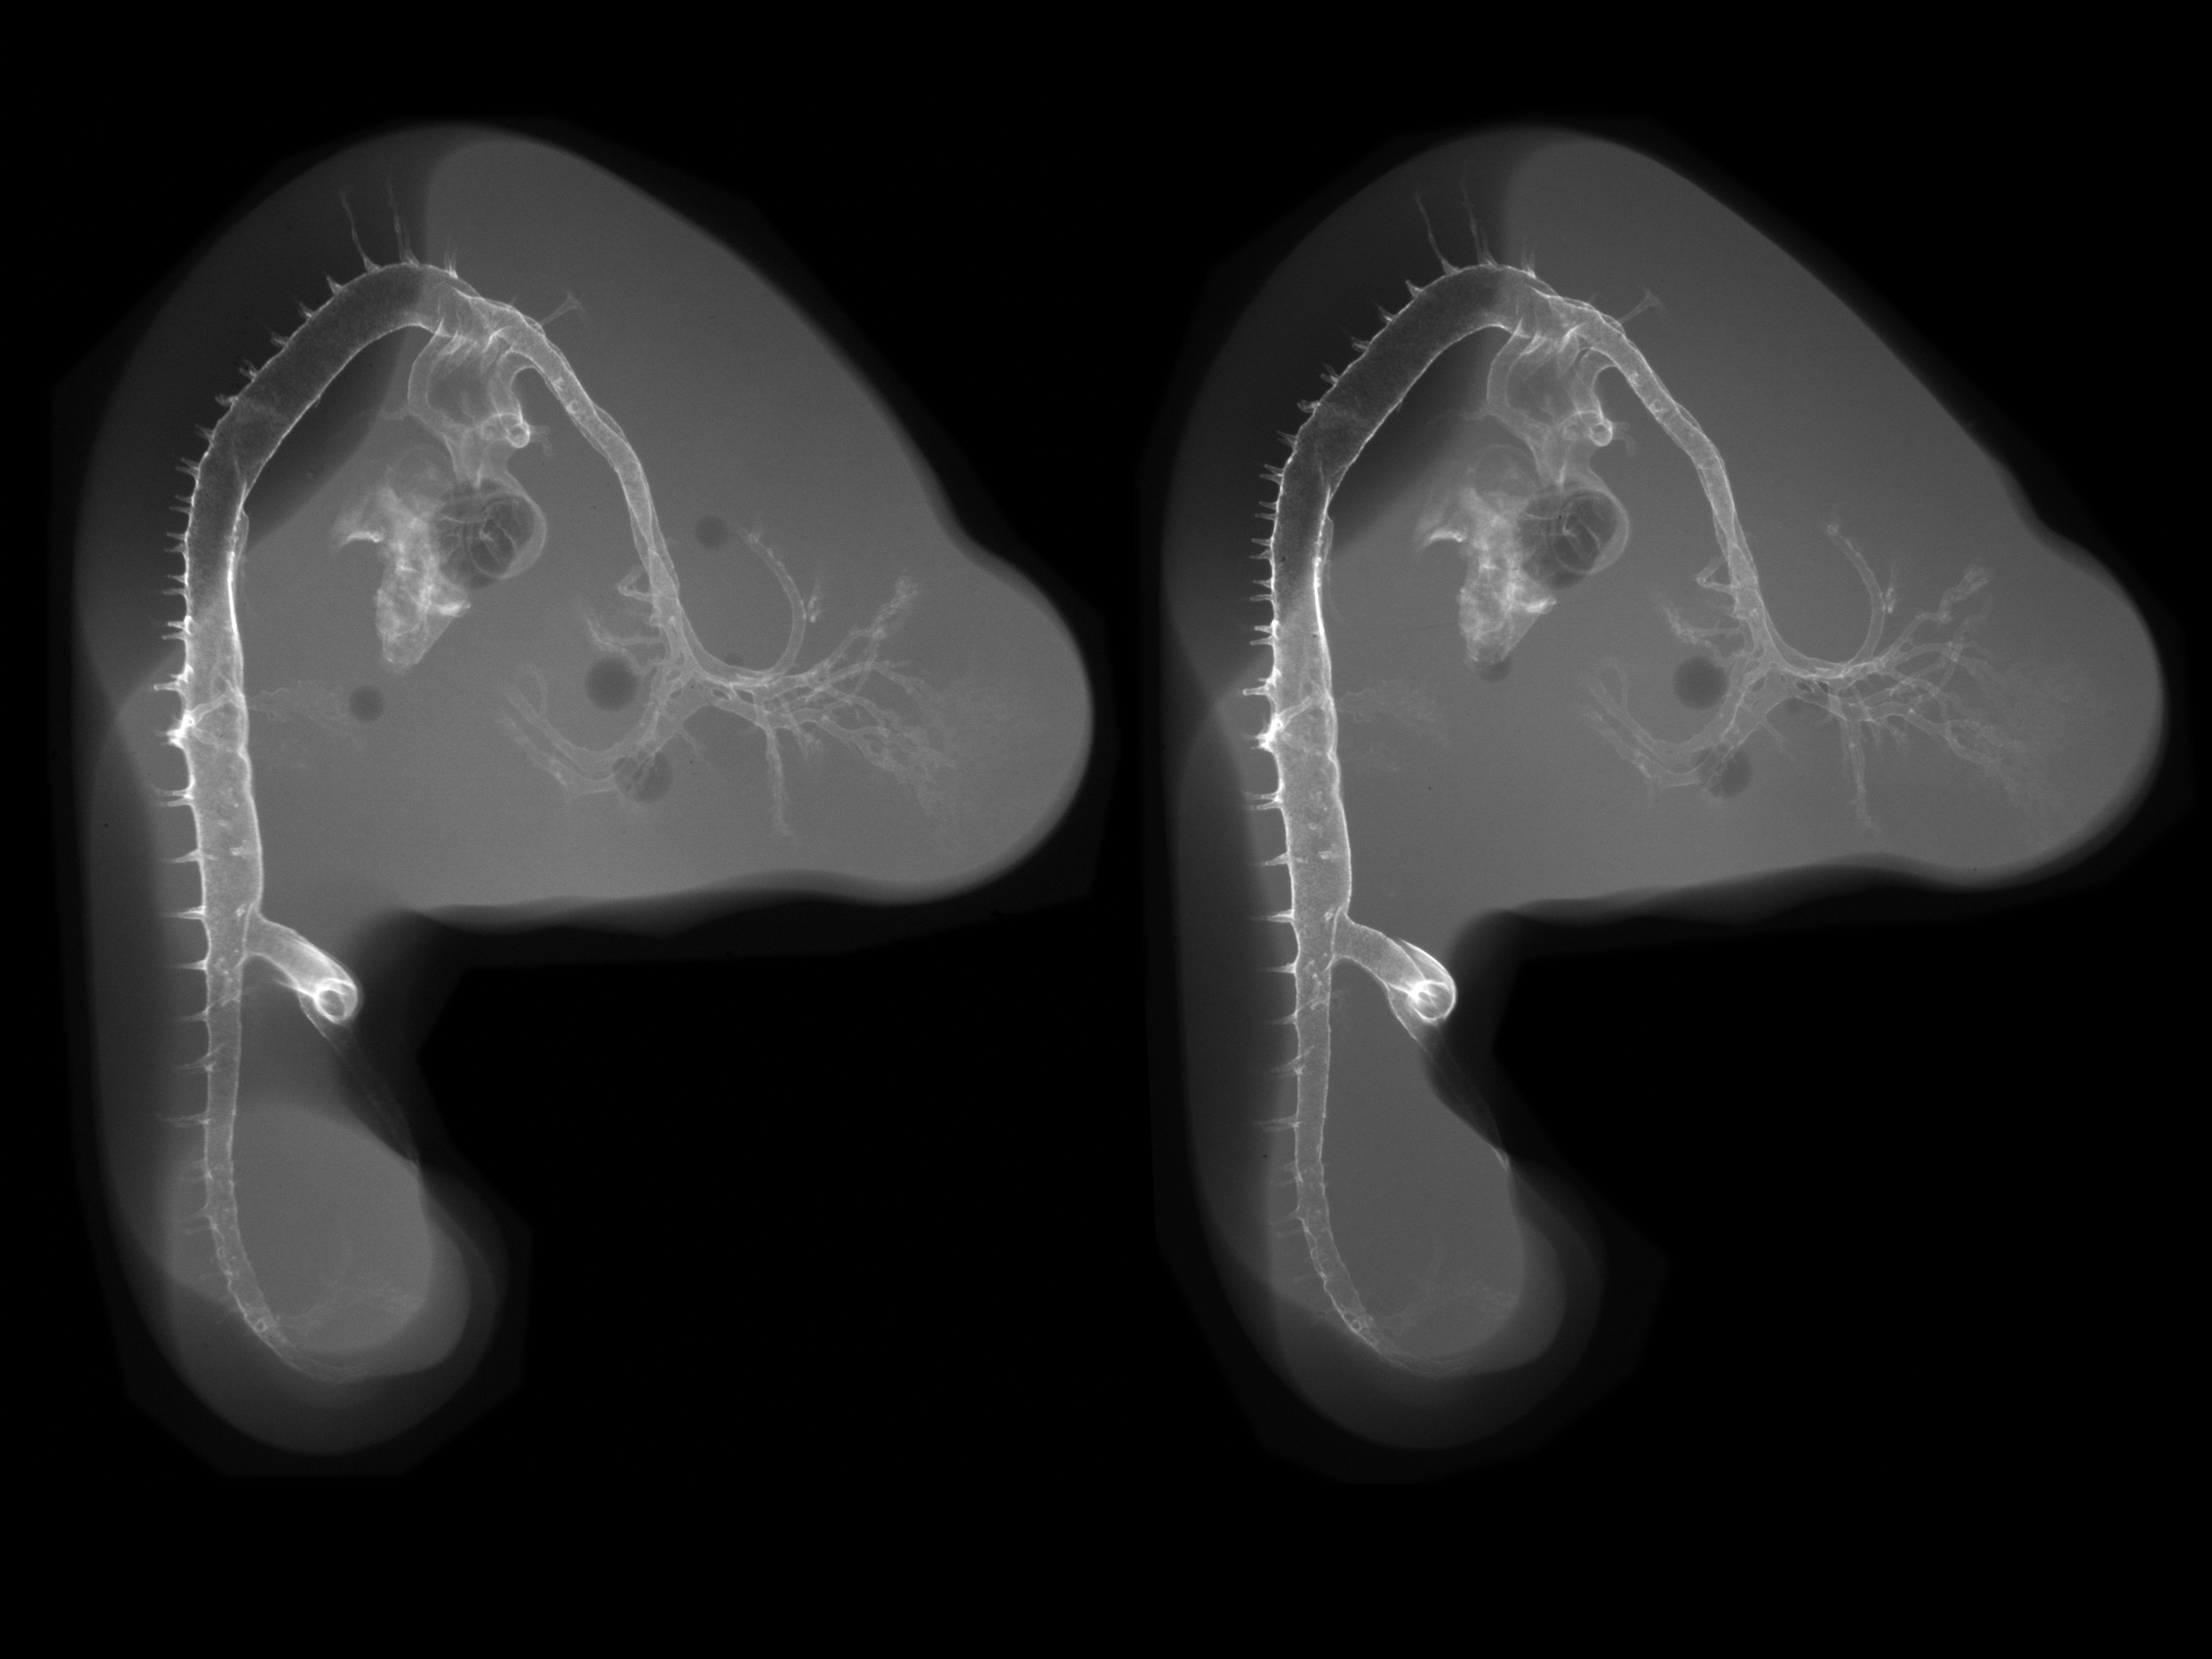

Hamburger-Hamilton (HH) Stage 23 (approx. 4 days)

Stereo X-Ray Micrographs